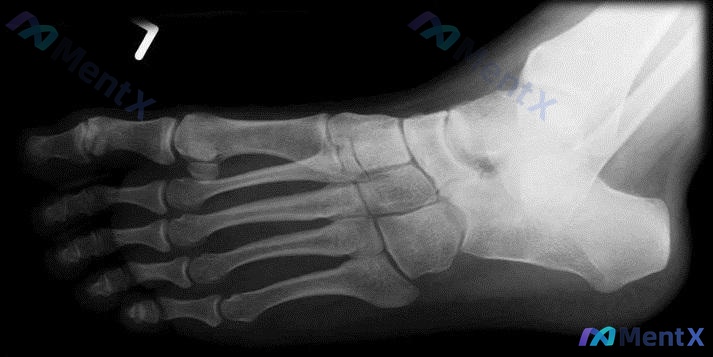

整理了一份青少年足痛病例资料,有几个点比较值得讨论。 患者信息:14 岁女孩 主诉:双足疼痛 6 个月,特别是跗骨窦区域。 查体:站立位及脚跟抬高测试显示足底内侧纵弓明显降低,足跟外翻畸形。 影像:左脚 X 光片证实内侧纵弓塌陷,距舟关节对合关系改变,未见明显骨折或骨质破坏。 讨论点: 1. 青少年...